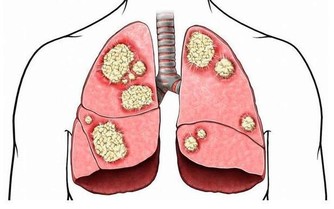

毒素不清,會累積成癌

在大腸癌的發生部位和發生機率中,

直腸和乙狀結腸得癌症的機率最高,

幾乎有百分之七十的腸癌

都集中從肛門上來六十公分的這一段,

因為這裡是宿便最容易囤積的地方,毒素都累積在這裡,

這段腸子就像家裡的垃圾桶,等到垃圾積滿了才會去倒。

咖啡灌腸最主要就是針對這一段腸道進行清腸排毒。

腸癌目前高居國人癌症發生人數的第一名,

是有跡可循的,證明現代人飲食中的毒素真的太嚴重,

加上排泄不良,宿便的毒素都累積在大腸內。